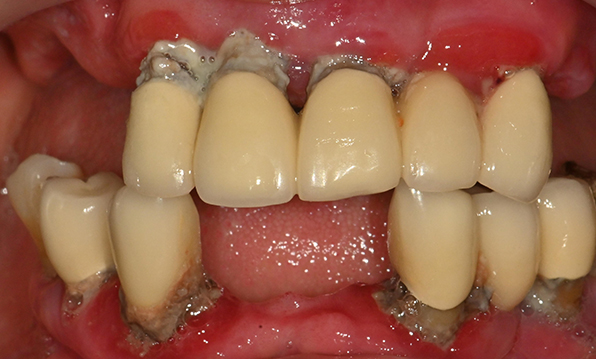

Case 03

Before After